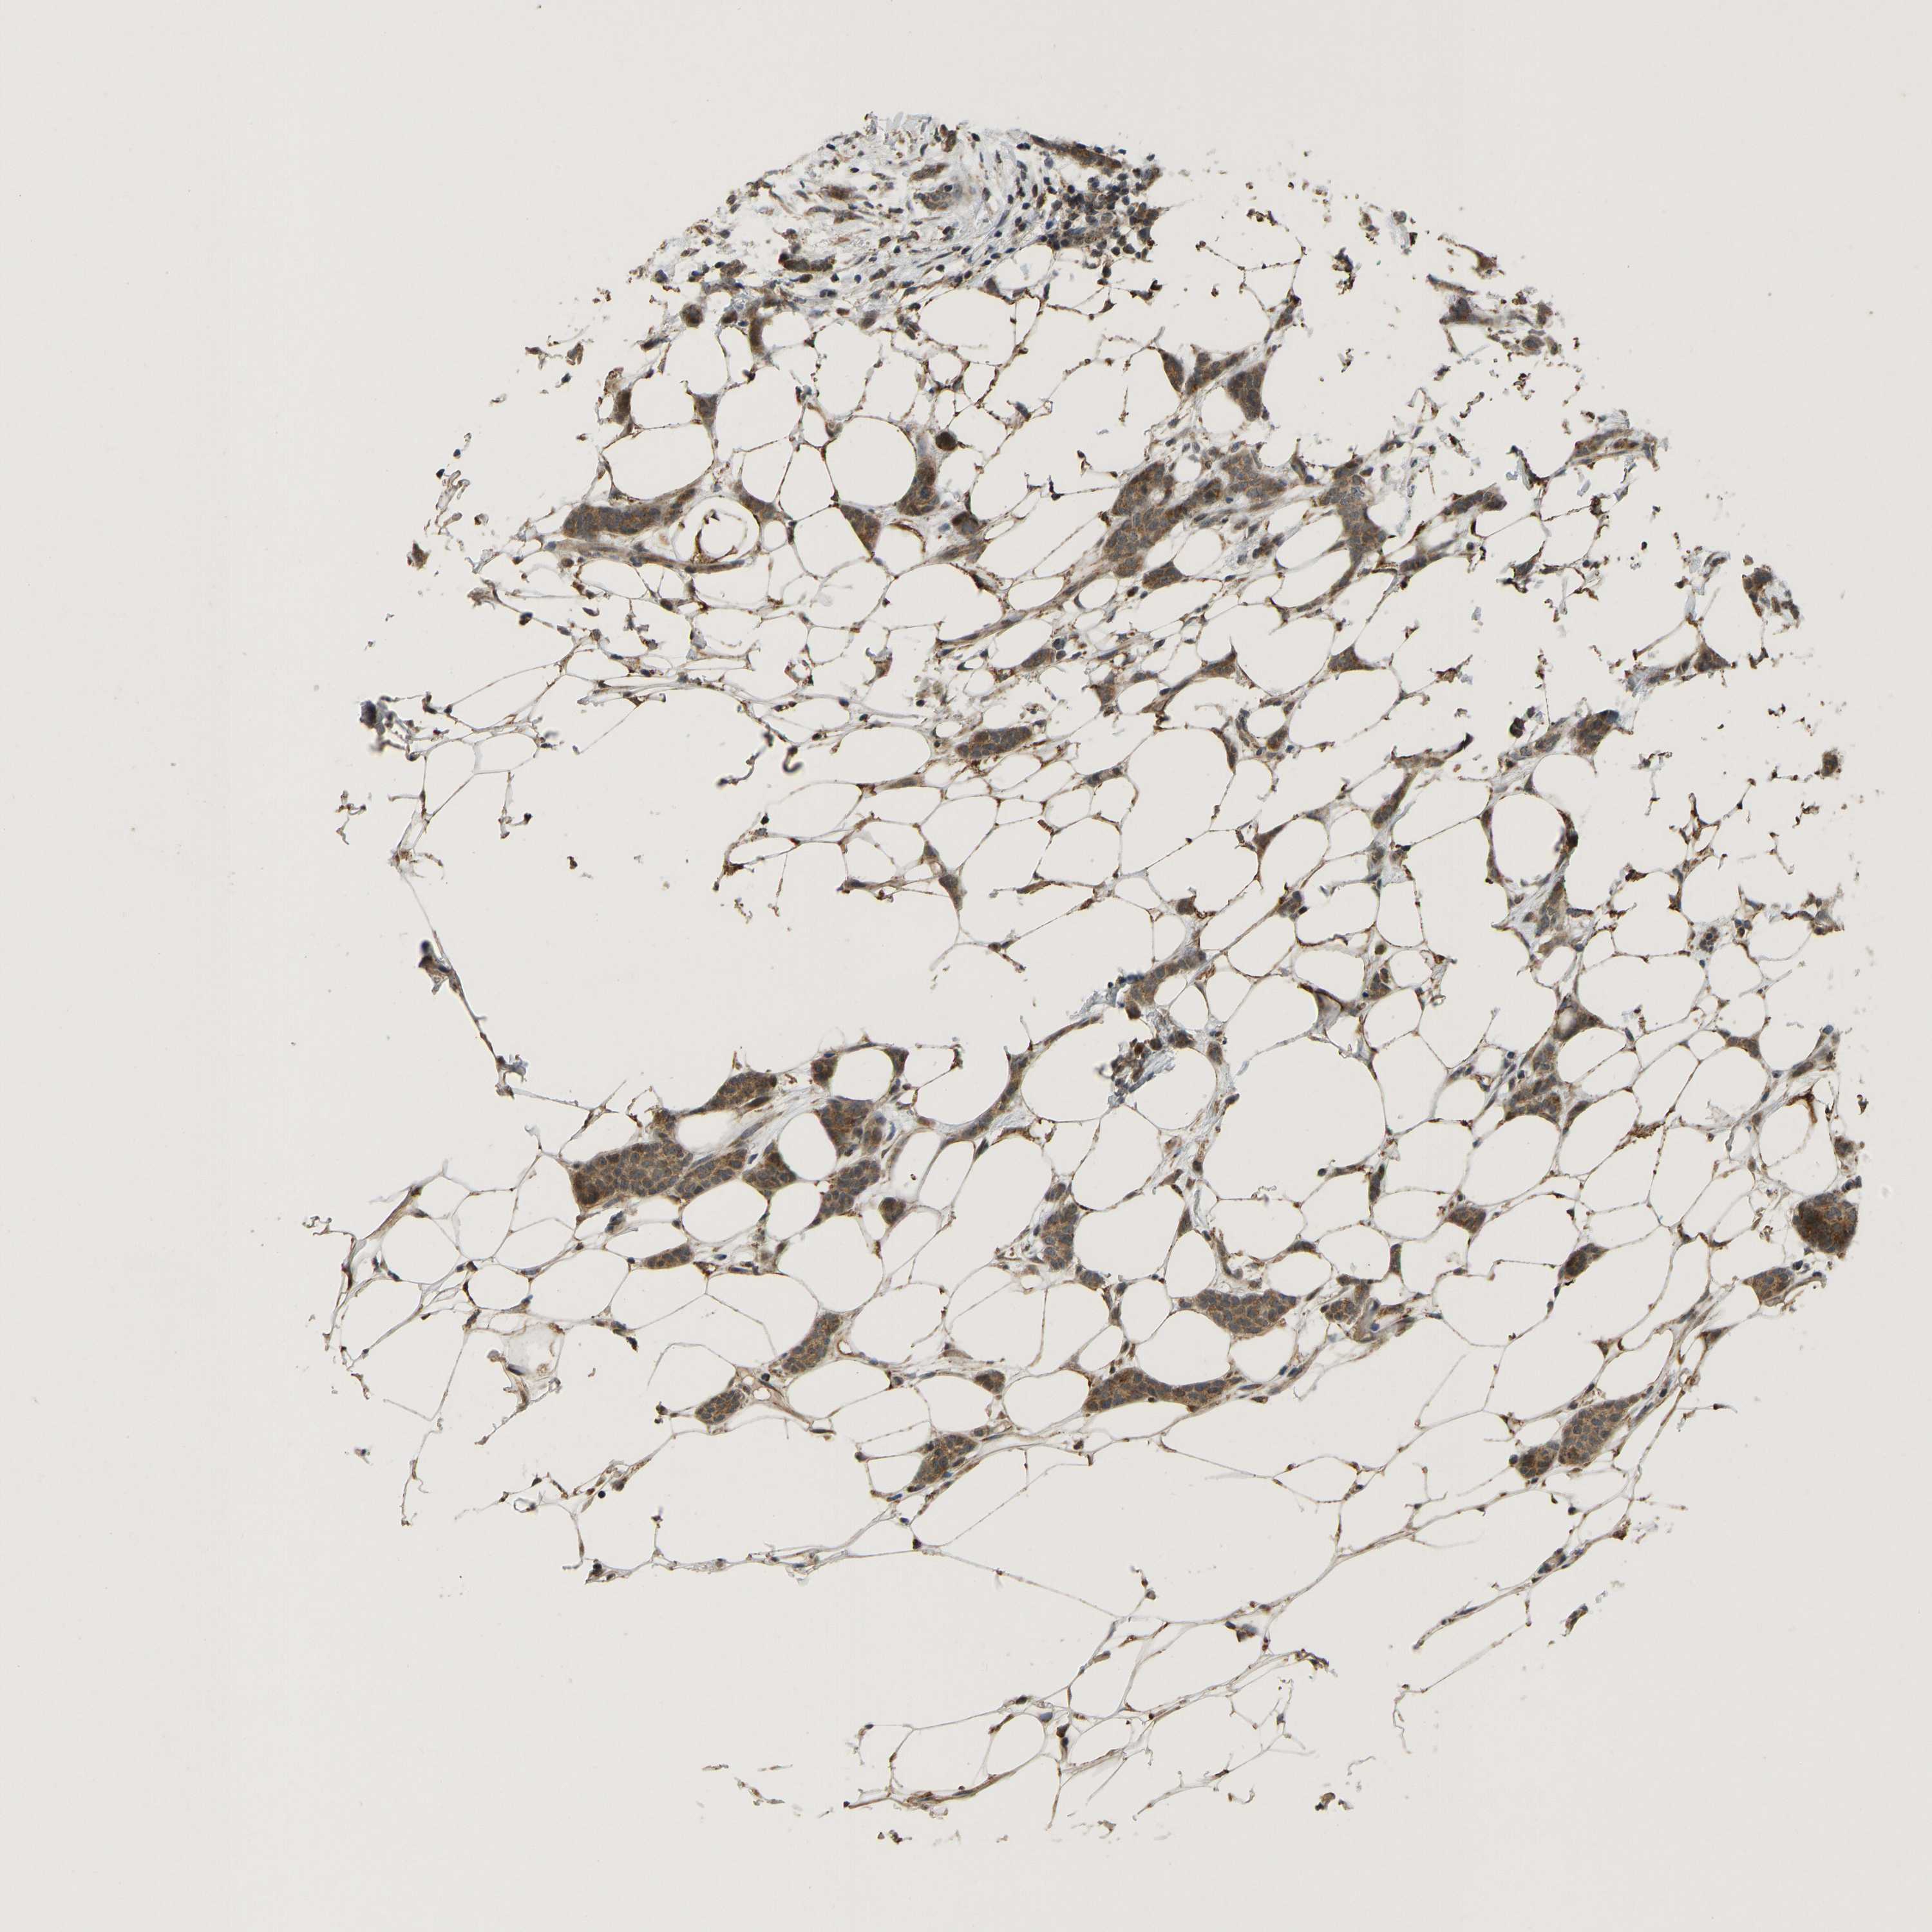

BRCA TCGA BRCA VALIDATION PROTEIN EXPRESSION

ANTIBODIES

AND

VALIDATION